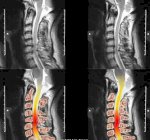

Chụp X Quang Chẩn Đoán Thoái Hóa Cột Sống